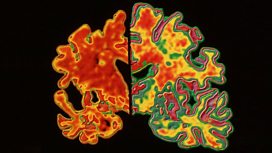

Dementia

We take a look at the 100 things we’re told you can do to prevent you getting Alzheimer’s